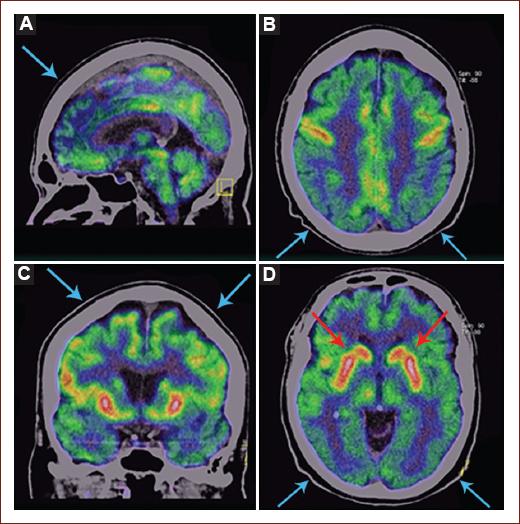

MRI was available in three patients, neither of whom presented any brainstem abnormalities (Fig. 1). One patient underwent 18F-FDG PET-CT, showing generalized cortical hypometabolism; hypermetabolism was visualized in the striatum (St) bilaterally (Fig. 2).

Figure 2 An illustrative brain [F18-FDG-PET scan obtained from patient 1 at 4 weeks after onset of symptoms. A-D: sagittal, axial, coronal, and axial views showing regions of hypometabolism including the occipital lobe (OL), parietal lobe (PL), and frontal lobe (FL) bilaterally, cerebellum and brainstem (blue arrows). Hypermetabolism visualized in the striatum (St) bilaterally (red arrows). Metabolic patterns were visualized using TrueD (Siemens, Medical Solutions, Germany).

In recent years, 18F-FDG PET-CT has been used in the diagnosis of primary brain autoimmune processes; with the most applicability to NMDA autoimmune encephalitis16. There is less information on the utility of 18F-FDG PET-CT in other autoimmune diseases of the CNS, and to the best of our knowledge, this diagnostic modality has not been widely explored in BBE. One patient in our study underwent 18F-FDG PET-CT, and it demonstrated cortical hypometabolism including the occipital lobe, parietal lobe, and frontal lobe bilaterally; cerebellum and brainstem. Even though the diagnosis of BBE remains clinical and serological, the 18F-FDG PET-CT may be useful in the diagnosis and follow-up of these patients, but more studies are needed.

The frequency of BBE in our population is very low (1.7%). IgM GM2 is another antiganglioside antibody related to BBE. Imaging studies such as MRI frequently do not present abnormalities and [F18-FDG-PET scan might be a useful study to describe a metabolism pattern to aid the diagnosis of BBE.